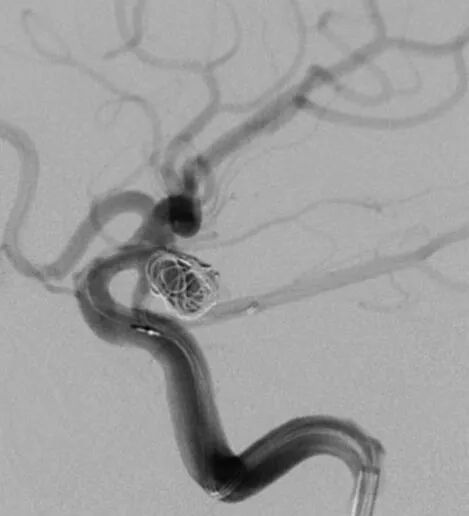

释放后的造影。突入颈内动脉和后交通动脉内的弹簧圈被压入瘤体内

继续填塞,后面就简单了。最后的结果,一共用了四枚弹簧圈,栓塞致密,瘤体及破口都不显影了